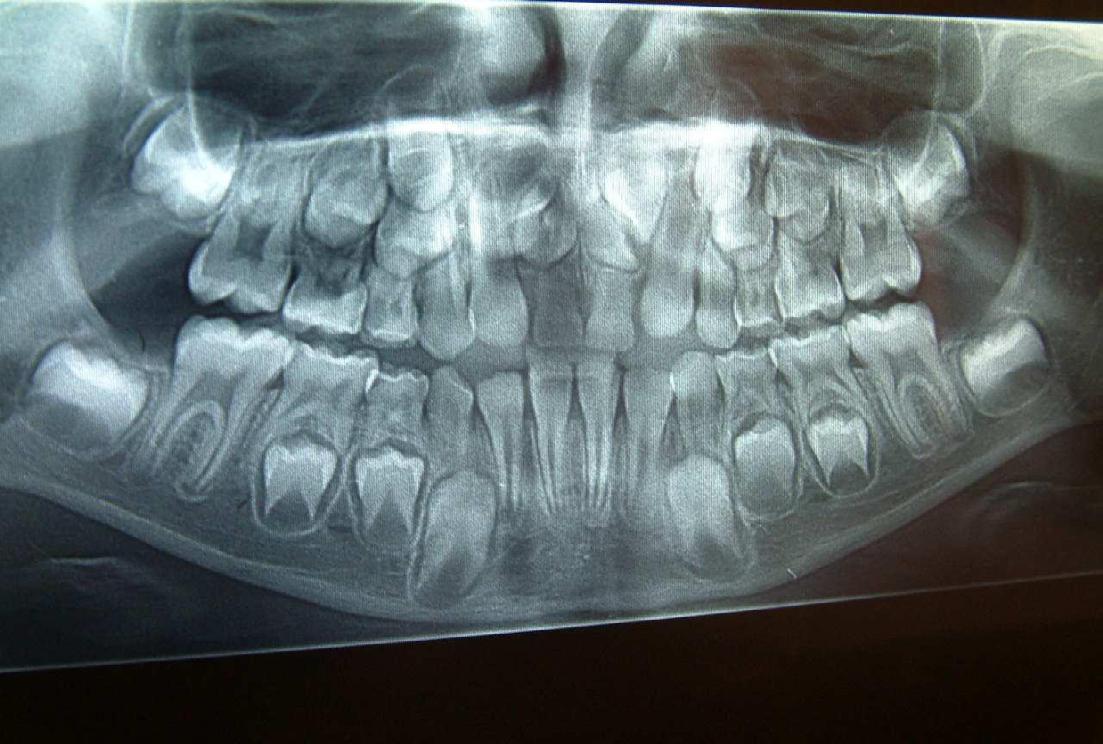

Στην ηλικία των 7 ετών, σύμφωνα με τις οδηγίες της Αμερικανικής Ορθοδοντικής Εταιρείας AAO (American Association of Orthodontics), καλόν θα είναι να εξετάζεται κλινικά αλλά και ακτινογραφικά η κατάσταση της μεικτής οδοντοφυίας του παιδιού για σκελετική ή οδοντική ασυμμετρία των γνάθων, για ελλείποντα δόντια ή δυνητικώς έγκλειστα ή για παρουσία οδοντωμάτων ή για έκτοπη ανατολή

Γενετικώς ελλείποντα δόντια (ο άνω αριστερός πλάγιος, ο άνω δεξιός 2ος προγόμφιος, οι κάτω δεύτεροι προγόμφιοι αμφοτερόπλευρα.)

Μετά το πέρας της ορθοδοντικής θεραπείας, (2η φωτογραφία), τα κενά που δημιουργήθηκαν

από την έλλειψη των μονίμων δοντιών μετά την φυσιολογική απόπτωση των νεογιλών δοντιών, έκλεισαν με ορθοδοντική παρέμβαση

Στα 7 χρόνια του παιδιού εξετάζουμε με πανοραμική ακτινογραφία τη θέση των μονίμων άνω κυνοδόντων στο οστό και αναλόγως πράττουμε.